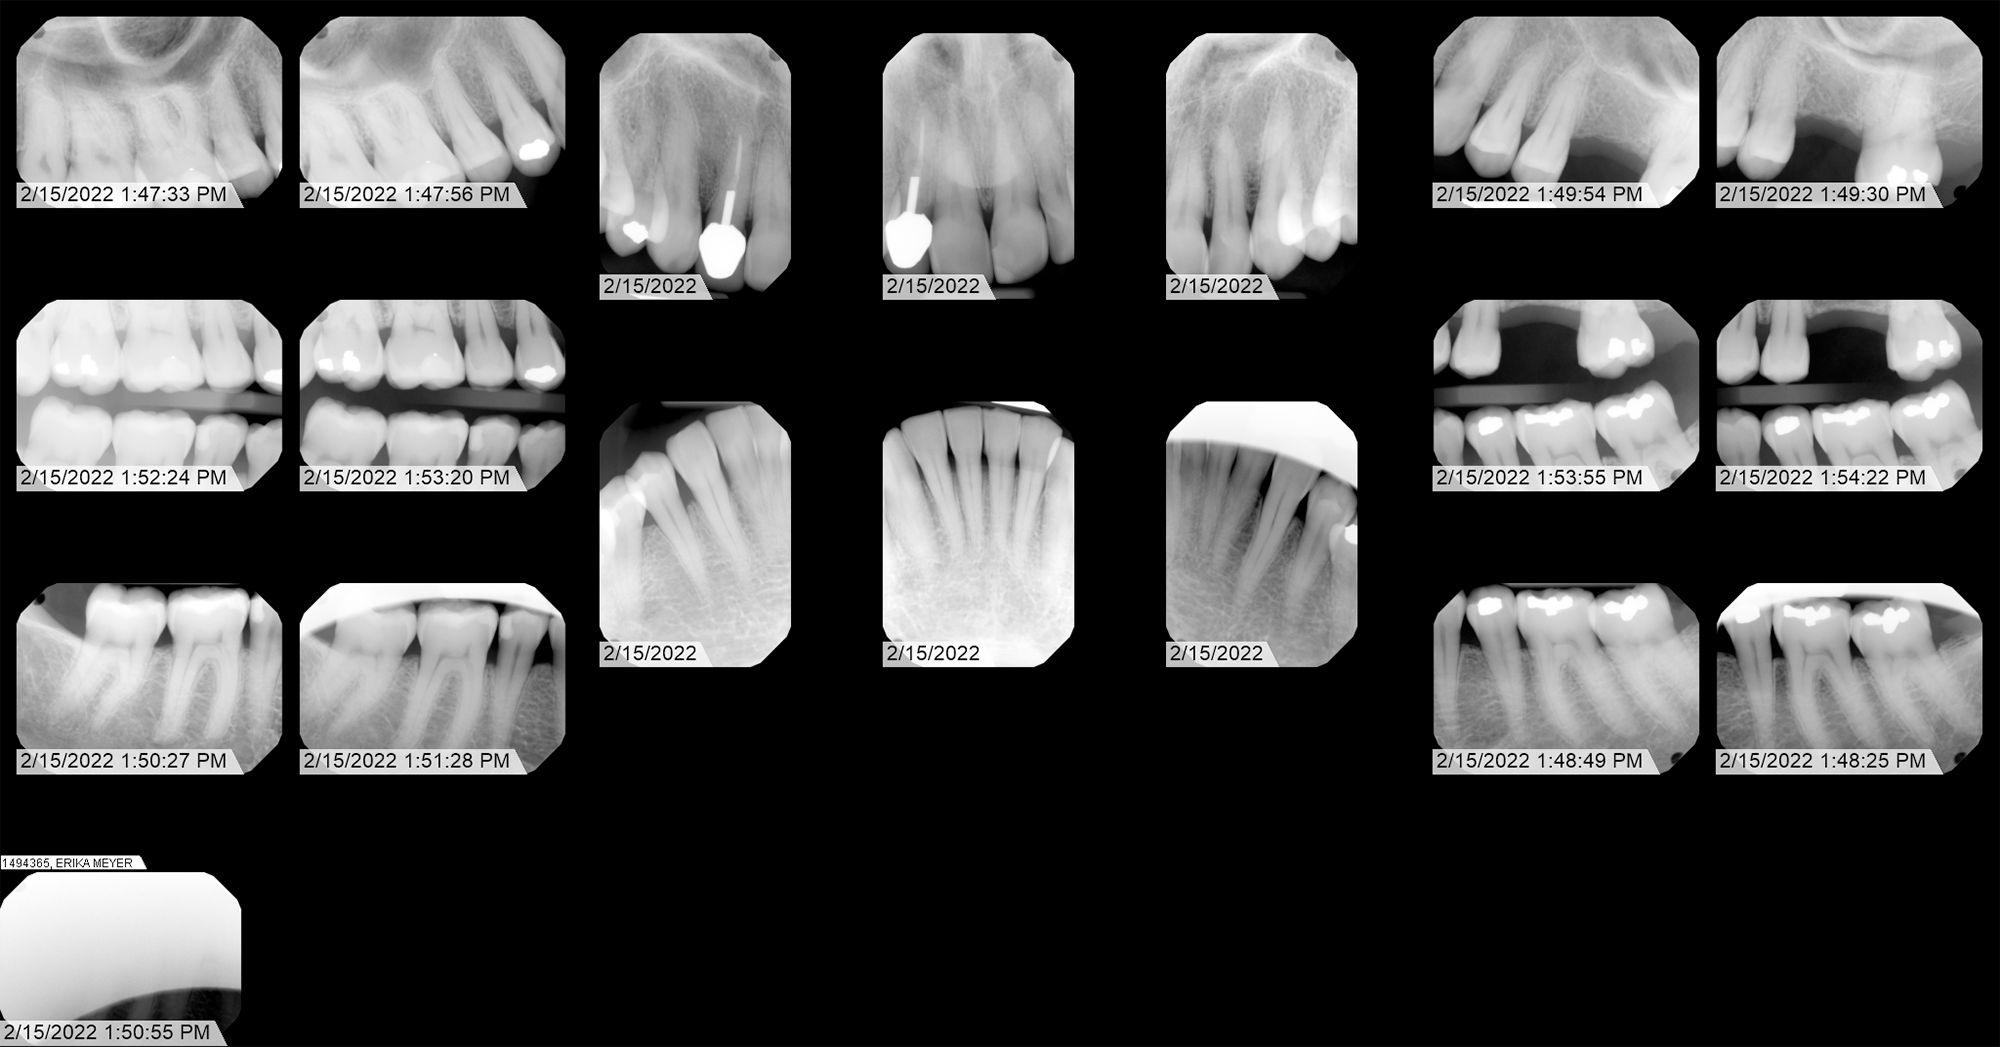

Radiographic Analysis (X-Ray)

Forensic identification of anomalous shape in extraction cavity.

Primary Exhibit

This featured x-ray, in my opinion, clearly shows an anomalous artifact embedded in my jawbone. This would have had to have been placed into the extraction cavity after the extraction and prior to suture. Dr. Patel is the only one who could have inserted this object - which appears to be a bioelectronic transceiver - into my jaw. Over time, the cavity fills with bone tissue, so the implant is now embedded in the jawbone.

Dental map showing numbered teeth. Tooth 14 extracted Jan 10, 2020